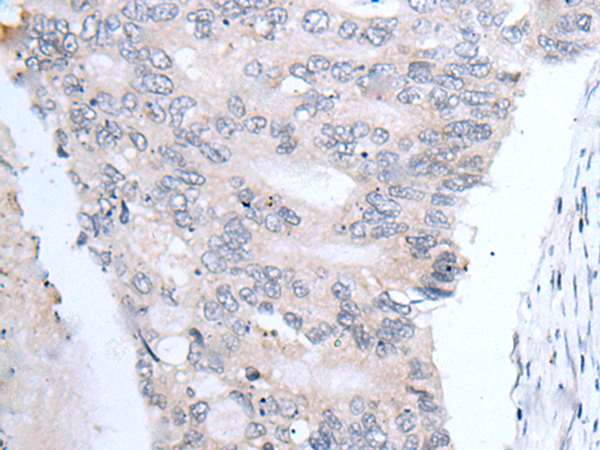

分类: 科研抗体货号: P12750别名: CBP1; CBP2; OI10; gp46; AsTP3; HSP47; PIG14; PPROM; RA-A47; SERPINH2应用: WB,IHC反应种属: Human, Mouse